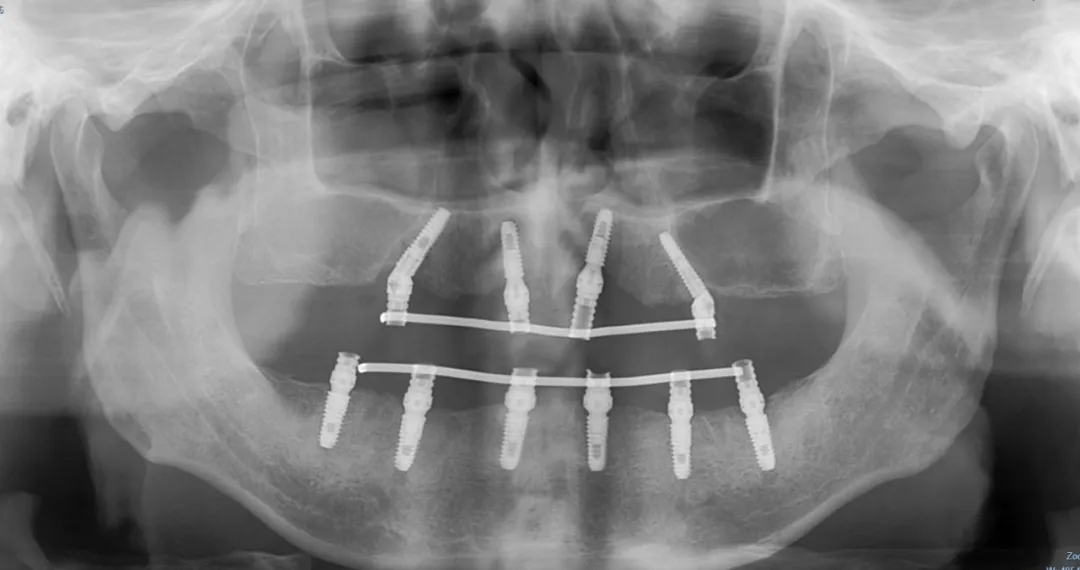

口腔科于淞主任接诊后,仔细查看了邢爷爷的口内情况和已有CT,确认其牙槽骨条件良好。针对患者“不想拔最后一颗牙”的诉求,团队综合评估后,为其制定了个性化下半口种植方案——采用ALL-ON-6技术,植入6颗ITI种植体,实现即刻负重。

在局部麻醉下,于淞主任精准操作:切开翻瓣、定位备洞、植入种植体、旋入基台与保护帽、缝合止血,同期为其制作戴入即刻临时义齿。整个过程稳妥高效,邢爷爷当天即拥有可用的半口牙列。术后,他感慨万分,特别感谢医大医院口腔科于淞主任及团队。一句“没想到仅三天时间,半口牙从仅存一颗到全齐”,道尽了他的惊喜。